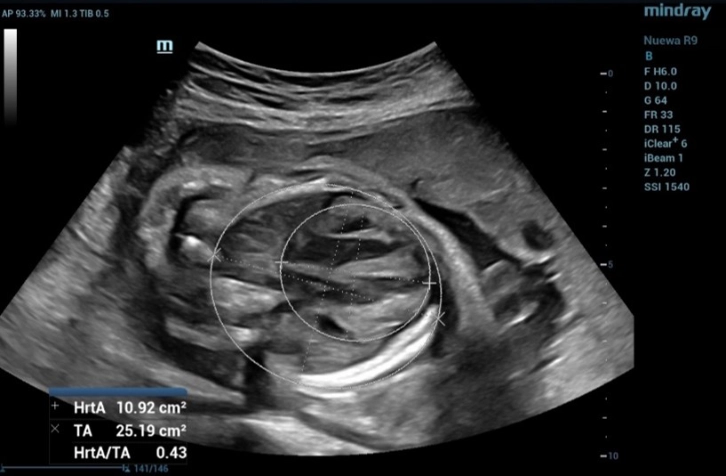

3. Cardiothoracic ratio (CTR)

Fetal cardiothoracic (C/T) circumference ratio is a parameter that can be used in the assessment of fetal cardiac and thoracic/chest wall anomalies. It represents the proportion between the circumference of the heart and that of the thorax, which can be appropriately measured during fetal ultrasound examinations.

The CTR measurement in this fetus, as shown in Figure 7, is 0.43, which is less than the cut-off value of 0.54.

the measurement of the CTR in fetus and the CTR value was 0.43

Figure 7 Shows the measurement of the CTR in fetus and the CTR value was 0.43